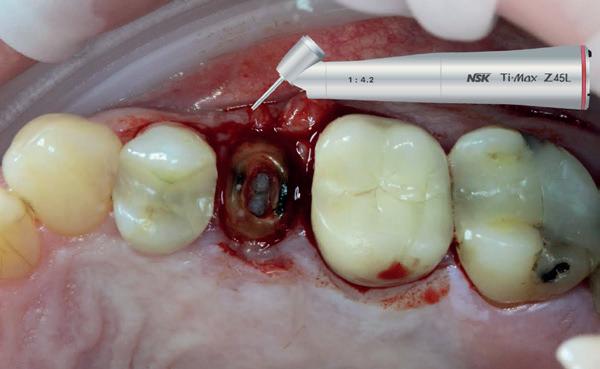

1. Afgebroken 24. Geen hoektandgeleiding aanwezig.

2. Decapiteren van het element en splitsen van de wortels.

3. Verwijderen van de radices.

4. Curettage en spoelen met een zoutoplossing.

5. Het ridge preservation protocol waarbij we proberen zoveel moge-

lijk bot te behouden met behulp van een xenograft.

6. De tijdelijke pontic, waarbij gebruikgemaakt wordt van de eigen afgebroken kroon en wat composiet. 7-10. Een full thickness flap osteotomie met hand plaatsing van een MegaGen AnyRidge Implantaat volgens protocol resulteerde in een

De implantaatplaatsing en de beslissende fout (afbeelding 1-13)

De extractie verliep voorspoedig, waarbij ik zoals al-

primaire stabiliteit van 60 Ncm.

11. Röntgenfoto ter controle van de plaatsing en de angulaire. Dit bone-level implantaat werd 4 mm onder de weke delen geplaatst.

12. Direct post-op. Een direct geplaatste tijdelijke kroon. Vastgezet met een torque van 20 Ncm en gehecht met prolene 5/0.

tijd probeerde de buccale botlamel intact te houden. Dit is cruciaal voor latere botbehoud en implantaatplaatsing. Na curettage en spoelen van de alveole beoordeelde ik de situatie opnieuw: de botcondities leken gunstig voor een immediaat implantaat.

Hier begon echter de cruciale fout in mijn klinisch besluitvormingsproces. In mijn streven naar maximale primaire stabiliteit - wetende dat immediaat belasten enkel mogelijk is bij hoge stabiliteit -on-

13. Röntgenfoto ter controle van de pasvorm van de direct geplaatste tijdelijke kroon.

derprepareerde ik de osteotomie. Dit betekende dat ik een iets te smal implantaatbed creëerde, in de hoop dat het implantaat stevig in het bot verankerd zou worden.

Op papier leek dit een logische stap: het MegaGen AnyRidge-implantaat dat ik koos, gaf me een stabiliteit van 60Ncm—een cijfer dat vertrouwen gaf in immediaat belasten. Maar in mijn enthousiasme had ik onvoldoende rekening gehouden met de biologische gevolgen van overmatige compressie.